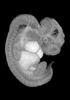

Carnegie Stage 17 (41 post-ovulatory days)

Most embryos at stage 17 are approximately 41 postovulatory days old and measure 11-14 mm in length. Distinguishing criteria for this stage include distinct digital rays in the hand plate, a rounded digital plate in the foot, a complete complement of hillocks on the mandibular and hyoid arches, distinct nasofrontal grooves, and a slight indication of a lumbar curvature.

This specimen does not represent normal development. The caudal nueral tube has failed to close properly.